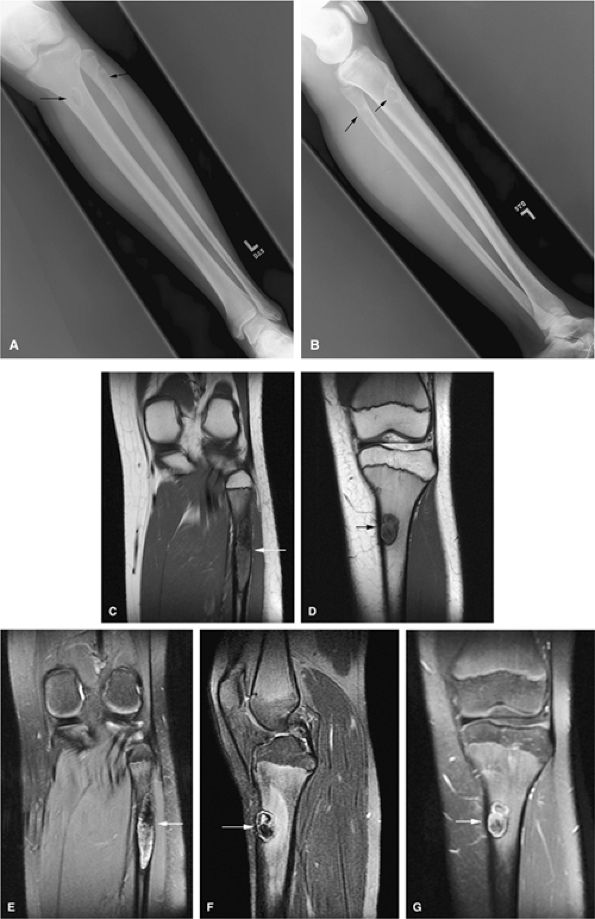

FIGURE 14-38 ● Anteroposterior (A) and lateral (B) radiographs show nonossifying fibromas in the proximal tibia and fibula (arrows). Coronal T1-weighted images (C and D) demonstrate the low-signal-intensity sclerotic border (arrows). Corresponding coronal (E) and sagittal (F) fat-suppressed T2-weighted fast spin-echo images show areas of hyperintensity (arrows). A contrast-enhanced fat-suppressed T1-weighted image (G) shows mild peripheral enhancement (arrow).